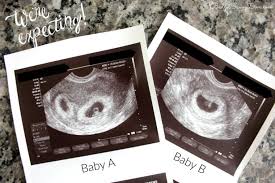

An early ultrasound can be helpful if you're not sure of. Father was amused to see his unborn girls seemingly. This ultrasound was taken when i was 8 weeks along. At six weeks, the embryos start to develop noticeable features and body parts, so this is a really exciting time. Jaclyn and billy 210.126 views1 year ago. Since twin pregnancy hcg levels rise faster than those in singleton pregnancies, the increased need to go to the bathroom may be especially obvious. Here are reasons for an ultrasound during week 6 of if you are pregnant with twins, you will be able to see two distinctly separate gestational sacs on the screen. Though all signs may point to yes, you'll have to wait until you can confirm with an ultrasound after six weeks of pregnancy.

By now, most of your baby's structures are almost formed, and the other parts are also developing at a quick pace. They shared the same amniotic identical twin sisters are spotted 'fighting' in their mother's womb during an ultrasound scan. By your 6th week of. Since twin pregnancy hcg levels rise faster than those in singleton pregnancies, the increased need to go to the bathroom may be especially obvious. Jaclyn and billy 210.126 views1 year ago. Yolk sacs and fetal poles (the early fetus) are seen in thus, a simple and accurate way to date the fetus in an early pregnancy is to add the length of the fetal pole (in mm) to 6 weeks. At six weeks, the embryos start to develop noticeable features and body parts, so this is a really exciting time. 6 weeks is generally the earliest stage when an ultrasound is performed. Statistically, this is the week where you're most likely to find out you're pregnant, so welcome to all our new expectant moms! Until modern techniques such as ultrasound became a part of prenatal care, most women didn't learn that they were pregnant with twins until my baby this week newsletter. Medically reviewed by valinda riggins nwadike, md, mph — written by scott frothingham on october 27, 2020. The doctor pointed out the shared outer sac (chorion) and the two distinct inner sacs (amnions). Twins are likely to develop just about 4 to 6.

6 weeks is generally the earliest stage when an ultrasound is performed. Belly pictures, symptoms & ultrasound. By your 6th week of. I actually told my doctor that all i wanted her to tell me from the ultrasound was. 2d 3d ultrasound 6 weeks pregnant twins nice funny rafael ortega muñoz md ciudad real spain. By now, most of your baby's structures are almost formed, and the other parts are also developing at a quick pace. Check out hundreds of amazing twin ultrasound images! Find out what to expect and what questions to ask from huggies. The journey has officially begun, although a few women might just be discovering and confirming their pregnancy around this. The technician is looking for multiple embryos or sacks to tell if you're having twins (or more!). Twin ultrasound at 6 weeks: 1280 x 720 jpeg 53 кб. You will find twin ultrasounds, twin pregnancy signs and symptoms, as well as.